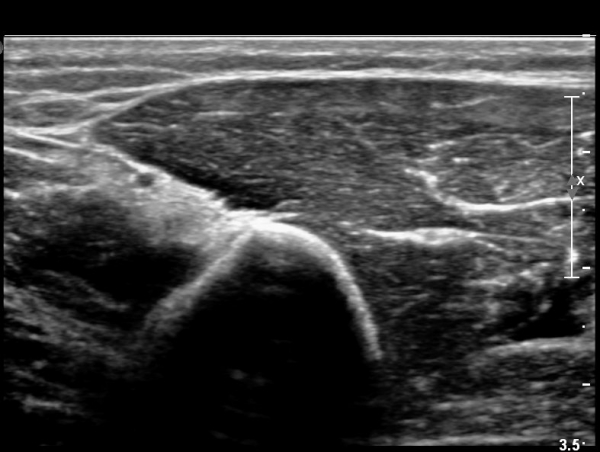

ŽÃËÀÚ¸¦ Á¶±Ý ¸»´ÜÀ¸·Î À̵¿ÇÏ´Ï ¿ä°ñ½Å°æ Àú¿¡ÄÚ ºÎÁ¾ÀÌ ´õ¿í ¶Ñ·ÈÇѵ¥(»çÁø 2),

ŽÃÊÀÚ¸¦ Á¶±Ý ´õ ¸»´ÜÀ¸·Î À̵¿ÇÏ´Ï ¿ä°ñ½Å°æÀÌ °üÂûµÇÁö ¾Ê°í(»çÁø3),